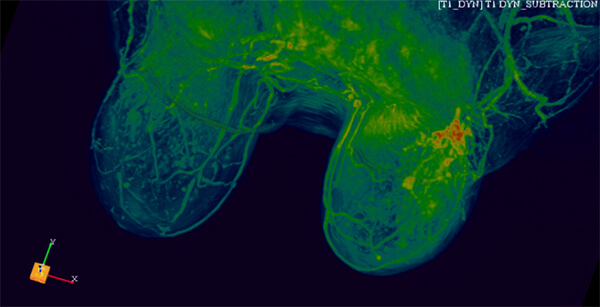

Τρισδιάστατη απεικόνιση ταχείας πρώιμης αιμάτωσης μαστών

- Δυναμική αγγειογραφία (4D time resolved TWIST)